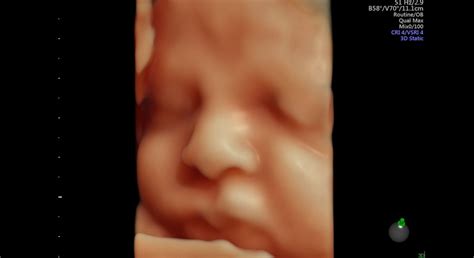

Neliečená alebo nedostatočne kompenzovaná tehotenská cukrovka predstavuje významné riziko nielen pre matku, ale najmä pre vyvíjajúci sa plod. Výkyvy hladín krvného cukru sú nebezpečné v každom štádiu tehotenstva.

V prvom trimestri, keď dochádza k formovaniu orgánov plodu, môže vysoká hladina cukru viesť k vrodeným vývojovým chybám (diabetická embryopatia), ako sú vrodené chyby srdca, mozgu, obličiek a kostí. Medzi najzávažnejšie patrí syndróm kaudálnej regresie, ktorý ovplyvňuje vývoj panvy a dolných končatín. V tomto období hrozí aj riziko odumretia plodu.

V neskorších fázach tehotenstva môže nadmerná hladina glukózy v krvi matky stimulovať u plodu tvorbu inzulínu. Inzulín pôsobí ako rastový hormón, čo vedie k nadmernému rastu plodu (makrozómia), často s pôrodnou hmotnosťou nad 4 000 gramov. Tieto deti sa rodia s nadmerným podkožným tukom, čo môže sťažiť pôrod.